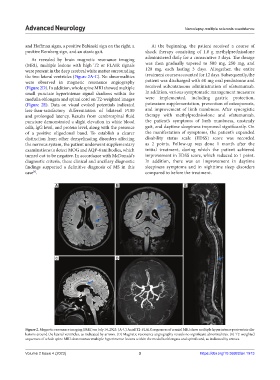

As revealed by brain magnetic resonance imaging administered daily for a consecutive 3 days. The dosage

(MRI), multiple lesions with high T2 or FLAIR signals was then gradually tapered to 500 mg, 250 mg, and

were present in the deep cerebral white matter surrounding 120 mg, each lasting 3 days. Altogether, the entire

the two lateral ventricles (Figure 2A-C). No abnormalities treatment course accounted for 12 days. Subsequently, the

were observed in magnetic resonance angiography patient was discharged with 60 mg oral prednisone and

(Figure 2D). In addition, whole spine MRI showed multiple received subcutaneous administration of ofatumumab.

small punctate hyperintense signal shadows within the In addition, various symptomatic management measures

medulla oblongata and spinal cord on T2-weighted images were implemented, including gastric protection,

(Figure 2E). Data on visual evoked potentials indicated potassium supplementation, prevention of osteoporosis,

Figure 2. Magnetic resonance imaging (MRI) on July 14, 2023. (A-C) Axial T2-FLAIR sequences of cranial MRI show multiple hyperintense periventricular

lesions around the lateral ventricles, as indicated by arrows. (D) Magnetic resonance angiography reveals no significant abnormalities. (E) T2-weighted

sequences of whole spine MRI demonstrate multiple hyperintense lesions within the medulla oblongata and spinal cord, as indicated by arrows.